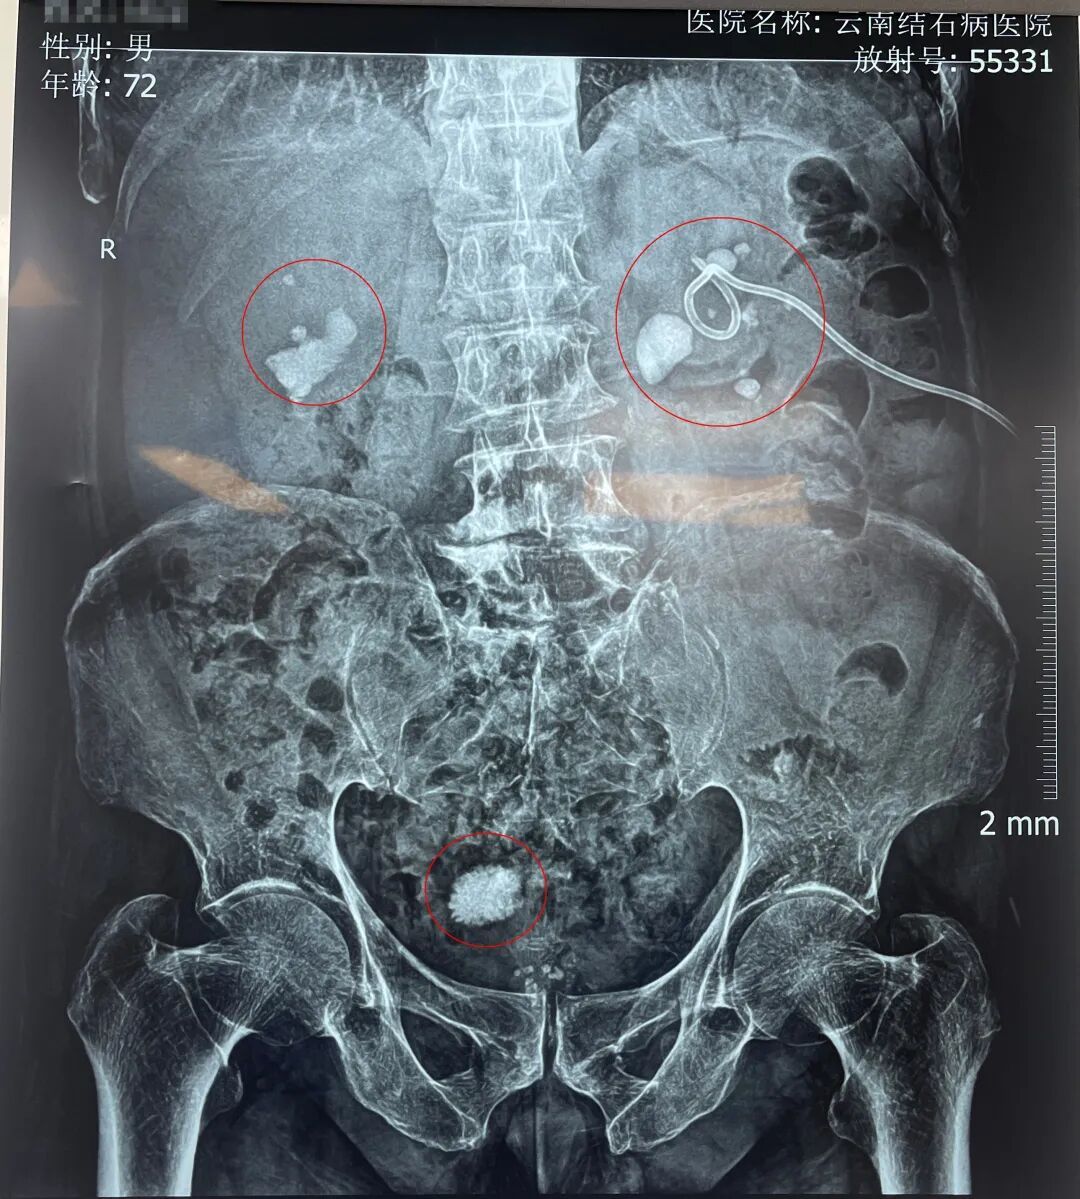

入院后,黄鸿宾主任为周爷爷安排了全面系统的检查。结果显示,其身体状况犹如一座年久失修的老屋,多处功能受损:前列腺增生伴钙化、膀胱结石、双肾多发性结石伴积水、脂肪肝、高血压等。

周爷爷的检查片子

可谓“牵一发而动全身”,面对如此复杂的临床状况,黄鸿宾主任为其量身定制了个体化治疗方案,即采用“瑞梦”前列腺热蒸汽消融术+膀胱镜下碎石取石术+纤维软性肾镜碎石取石术。一次手术,解决了他前列腺增生、膀胱结石、双肾结石等多重病痛。